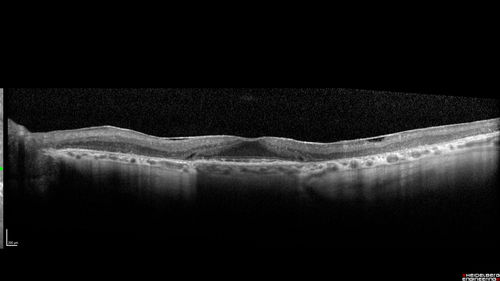

Concentric Geographic Atrophy - 76 year old man

Gradual vision loss, worse at night. VA 20/40 OU.